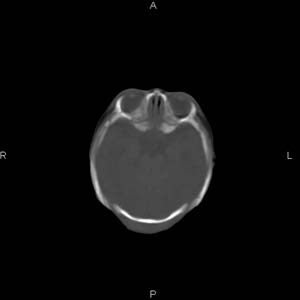

患者男,27天,出生后正常,今天中午在母亲怀里抱着吃奶在放下睡觉时发现后枕部慢慢出现一包块,来查头颅ct。无外伤史。包块内ct值47-51hu。请大家讨论。

皮下血肿,颅骨无缺如 ,颅缝无增宽。皮下血管破裂所因起。

头皮下血肿,局部枕骨略有凹陷

1脑膜膨出可能性大 2产伤所致枕骨骨缝分离、头皮肿胀不除外,

建议:枕骨(下部)薄层扫描。

枕部皮下血肿 局部枕骨凹陷

\"中午在母亲怀里抱着吃奶在放下睡觉时发现后枕部慢慢出现一包块,包块内ct值47-51hu。

颅骨无缺损,骨缝无增宽.支持头皮血肿(血管破裂)